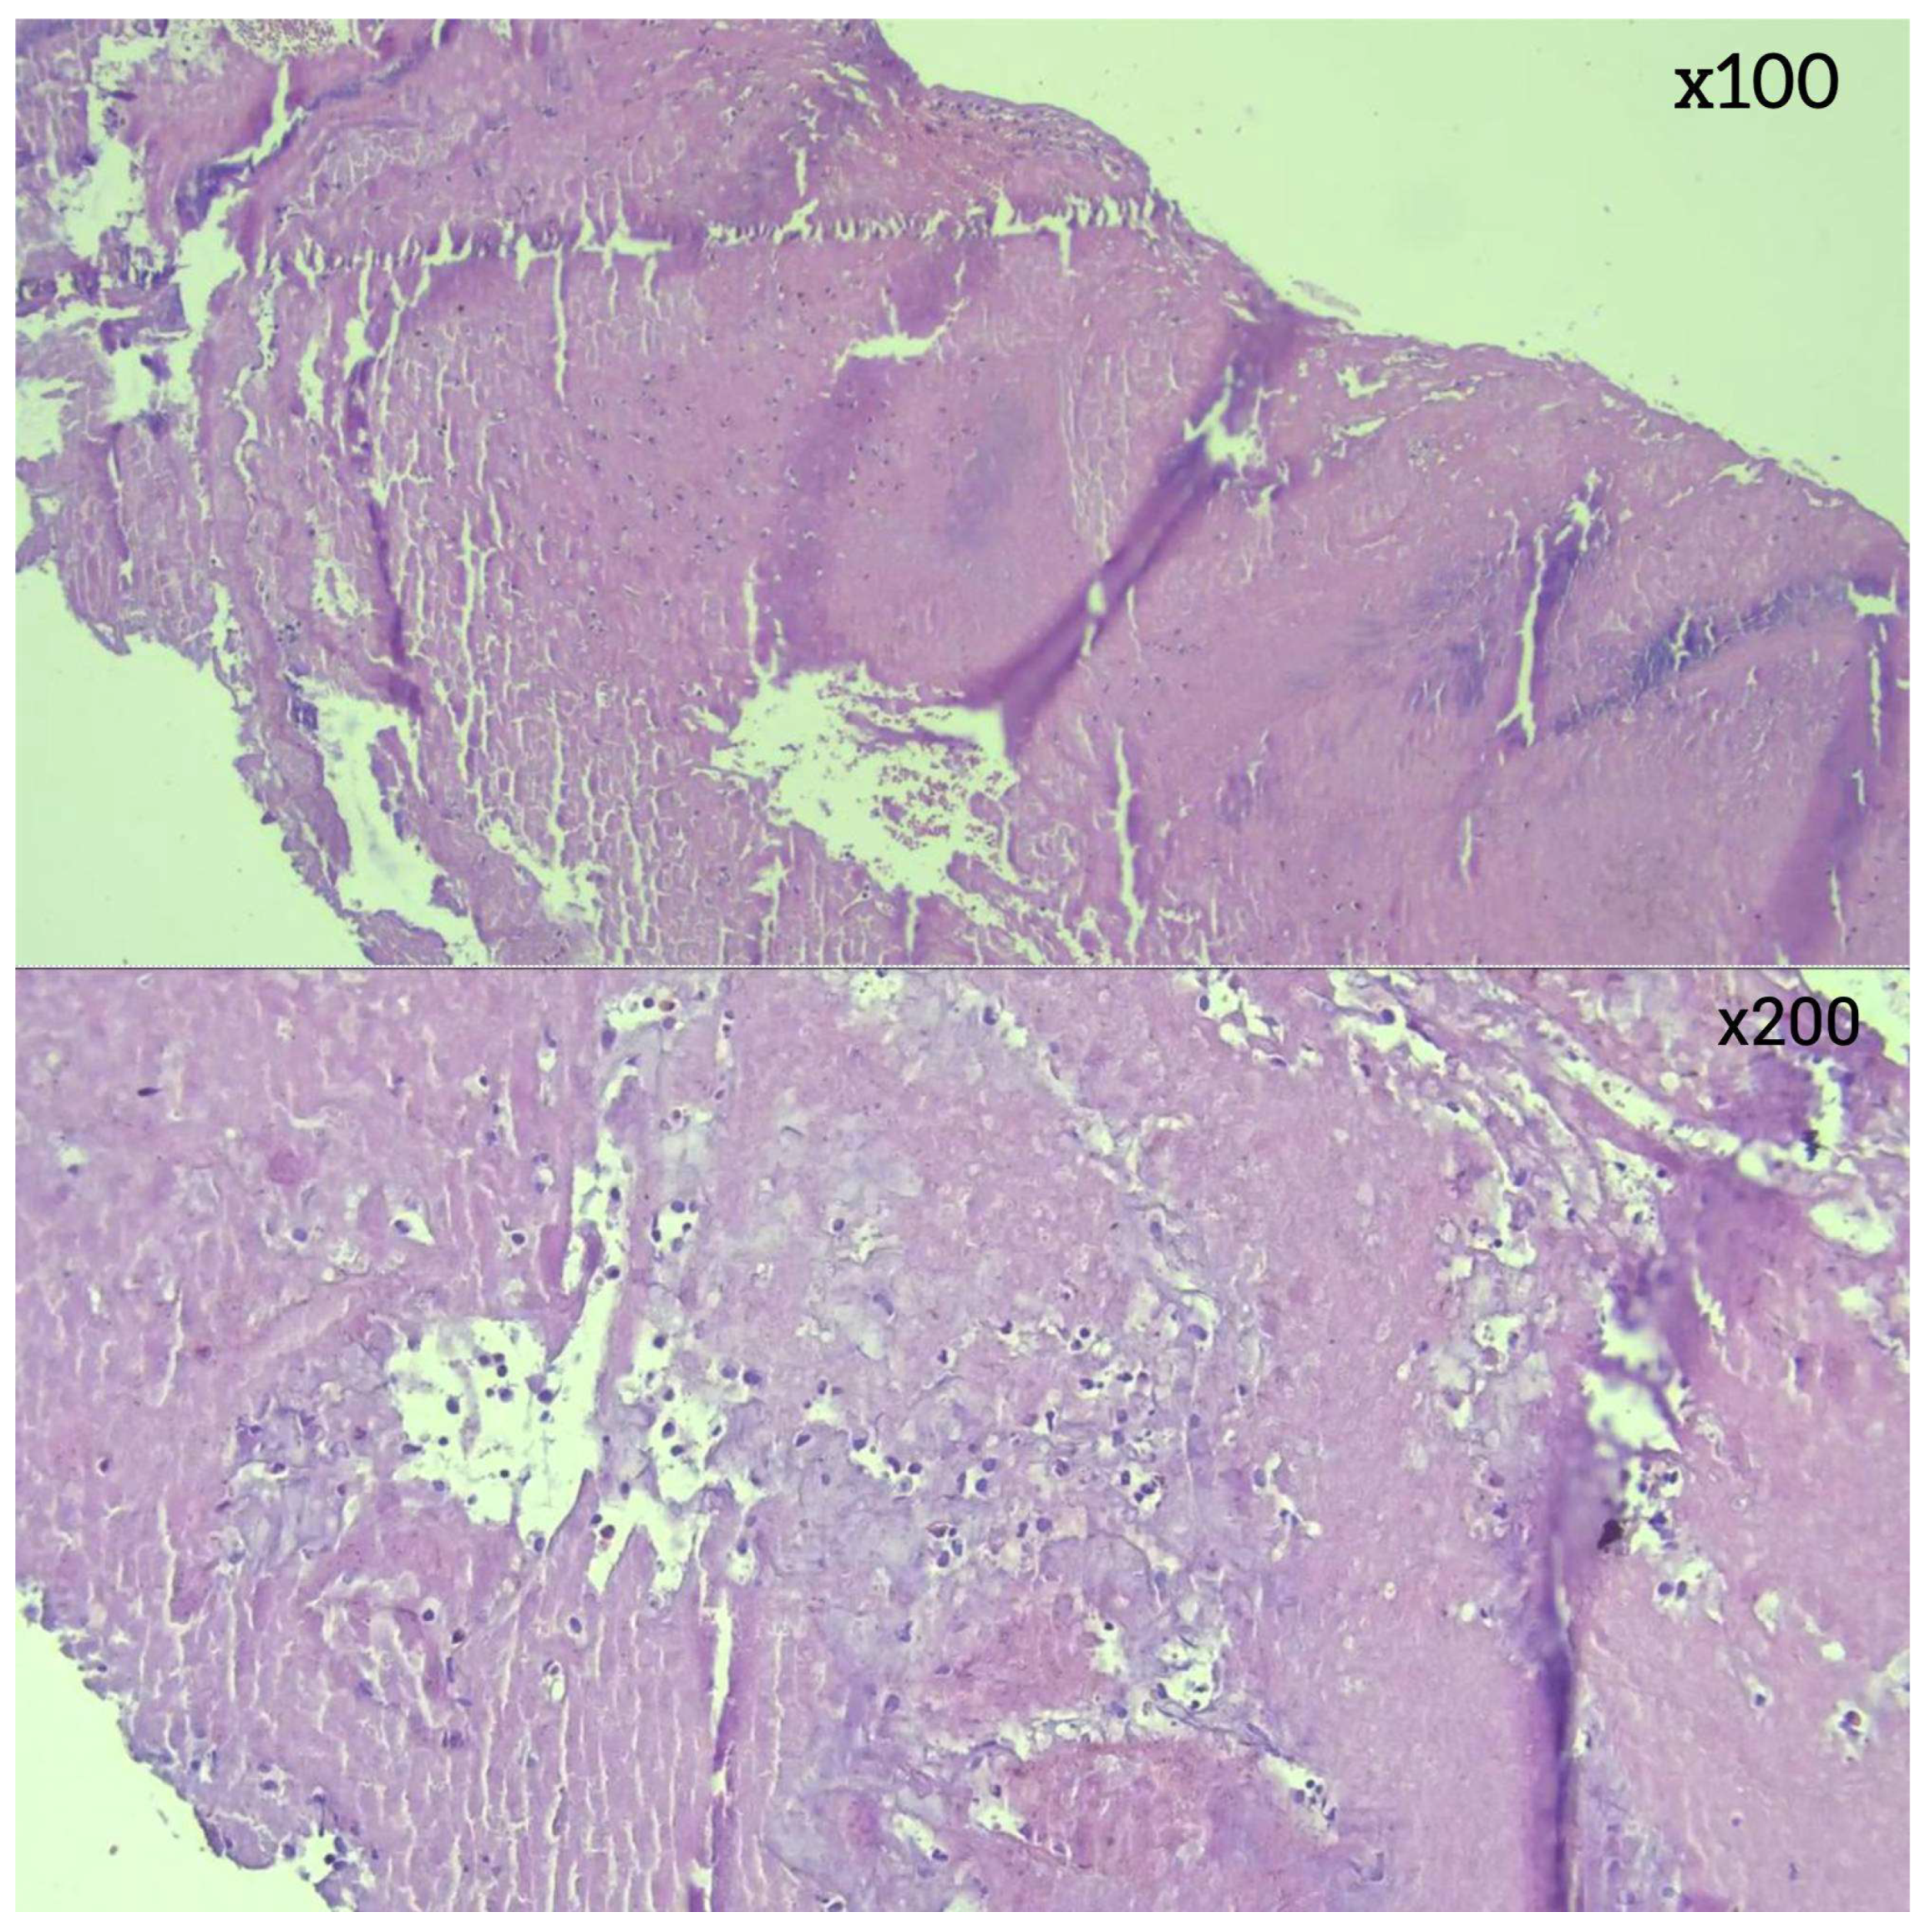

2.6. Histopathological Examination

| Early Stage | 40 (70.2%) | ||||||

| RBC-dominant | 28 (49.1%) | 14 (38.9%) | 3 (8.3%) | 15 (41.7%) | 2 (5.5%) | 2 (5.5%) | <0.001 |

| RBC = Fibrin | 12 (21.1%) | 10 (66.7%) | 4 (2.7% ) | 0 | 1 (6.7%) | 0 | <0.001 |

| Late Stage | 17 (29.8%) | ||||||

| Fibrin-dominant | 11 (19.3%) | 8 (66.7%) | 2 (16.7%) | 1 (8.3%) | 1 (8.3%) | 0 | <0.001 |

| Organized fibrin | 6 (10.5%) | 5 (55.5%) | 2 (22.2%) | 1 (11.1%) | 1 (11.1%) | 0 | <0.001 |